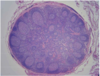

Normal LN

30

NHL- Follicular Lymphoma

31